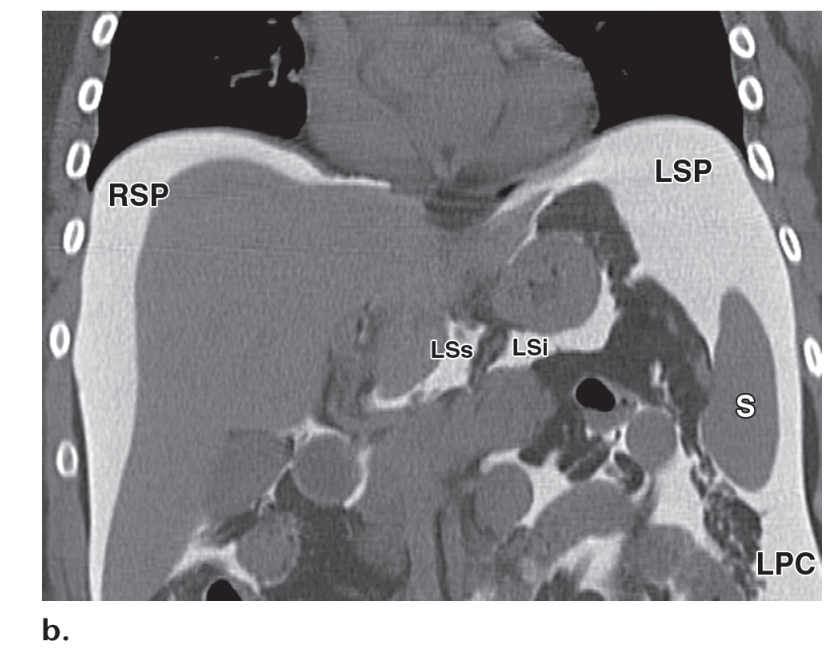

Fig. 2: Sagittal CT image shows inferior fusion of retromesenteric plane (RMP) with retrorenal plane (RRP) to form the combined interfascial plane (CIP). This point creates a route for spread of diseases between the abdominal and pelvic retroperitoneal spaces

Figure 13. Interfascial spread. (a) Diagram drawn in the sagittal plane shows the inferior fusion of the Gerota (GF) and Zuckerkandl (ZF) fascias, which form the combined interfascial plane (CIP). Although the perirenal space is cut off by the fusion of Gerota and Zuckerkandl fascias inferiorly, it is possible for disease to extend along the combined interfascial plane. (b) Coronal reformatted CT image obtained in a 75-year-old man with nonHodgkin lymphoma shows involvement of the left kidney (*) and perinephric space (black arrow) by tumor and thickening of Gerota fascia (white arrows). (c) Coronal CT image, obtained in the same patient, shows a nodule (arrow) in the combined interfascial plane (arrowhead), a finding indicative of interfascial spread of lymphoma.